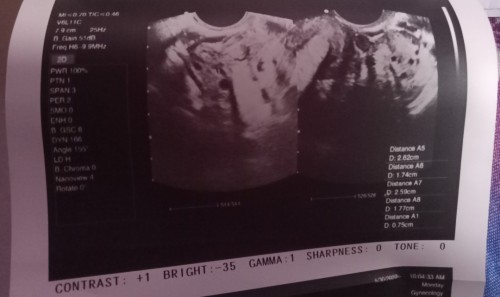

Transv result

Asking for my friend po Bali nagpatransv v po Kasi siya tapos Wala Naman po sinabi Yung doctor na nagtrans v sakanya ob kona daw Po mag eexplain Pagdating Naman po kay ob Sabi Po sakanya possible may pcos daw po siya pero payat Naman po Yung kaibigan po. Kaya medyo nagtataka po kami tapos nagpositive din Po Kasi siya sa pt non. Sabi ni ob po baka daw po early pregnancy pa lang daw po pinababalik po siya uli Ng ob para magpatrans v after ilang weeks nandiyan po Yung result at remarks Nung doctor medyo naguguluhan na po Kasi kami . Pinagtake po siya Ng folic acid#advicepls

Same case ko yan nag pt ako positive kaya nagpatingin ako kaso tele consultation lang sabi magpa transV ako while doing the ultrasound sabi no sign of pregnancy nung nakuha ko result polycystic ovaries bilateral and thickened endometrium ang impression. Ginawa ko nagpacheck ako sa iba after a week pinag pt ako positive kaya sbi nya transV pra macheck ulit sabi nya left ovary ko lang ang may pcos and positive na buntis ako 5weeks and 5days..early pregnancy daw kaya di agad nakita nung first ultrasound ko..para di ka mag worry try mo pacheck sa iba 🙂

Magbasa paAko nagpatransV ako ulit ksi nagpositive sa PT sis, around 3-4weeks pregnancy. Iyong PCOS ko lang din ang nakita, di pa kita sa transV kasi sabi nung sonoligists around 1500 HCG ang nakikita sa transV kung di pa ganun kataas HCG mo di pa talaga mkikita compare sa PT na magpositive na basta mas mataas sa 50 HCG. Bumalik ako around 5W3D kita na si baby and may heartbeat na. Take folic acid, kung nagtatry na magbuntis m, early pregnancy or buntis na. Di naman basihan kung mapayat ka para mag ka PCOS sis

Mi baka early pregnancy pa. Ganyan din sa kin, positive ako sa pt pero nung nagpa first tvs ako walang nakita. Thick endo lng tas mag cyst sa left ovary ko. Bumalik ako after 1month kasi ni monitor ko yung hcg level ko always positive naman sa pt and dun lng nakita na 8 weeks preggy ako nun withgood cardiac activity.

PCOS Nga po Yung nasa utz nyu. ganyan dinpo Yung akin almost 16 ako each ovary but at the same time Preggy din po Ako. bumalik Ako after 2 weeks to confirm the baby. Yung akin Kasi may sac kaya possible to have a fetus. and after 2 weeks na utz Meron na po fetus. nagtake na din Ako prenatal vitamins nun

looks like mine . gnyn din po transv ko my pcos din po ako pinag take ako ng folic and pampapayat. kc tumaba nga ako at nag possitive ako s pt. kya nong nag pacheck up ako nerequest ako ng ob n magpa transv. ayon pcos nga.